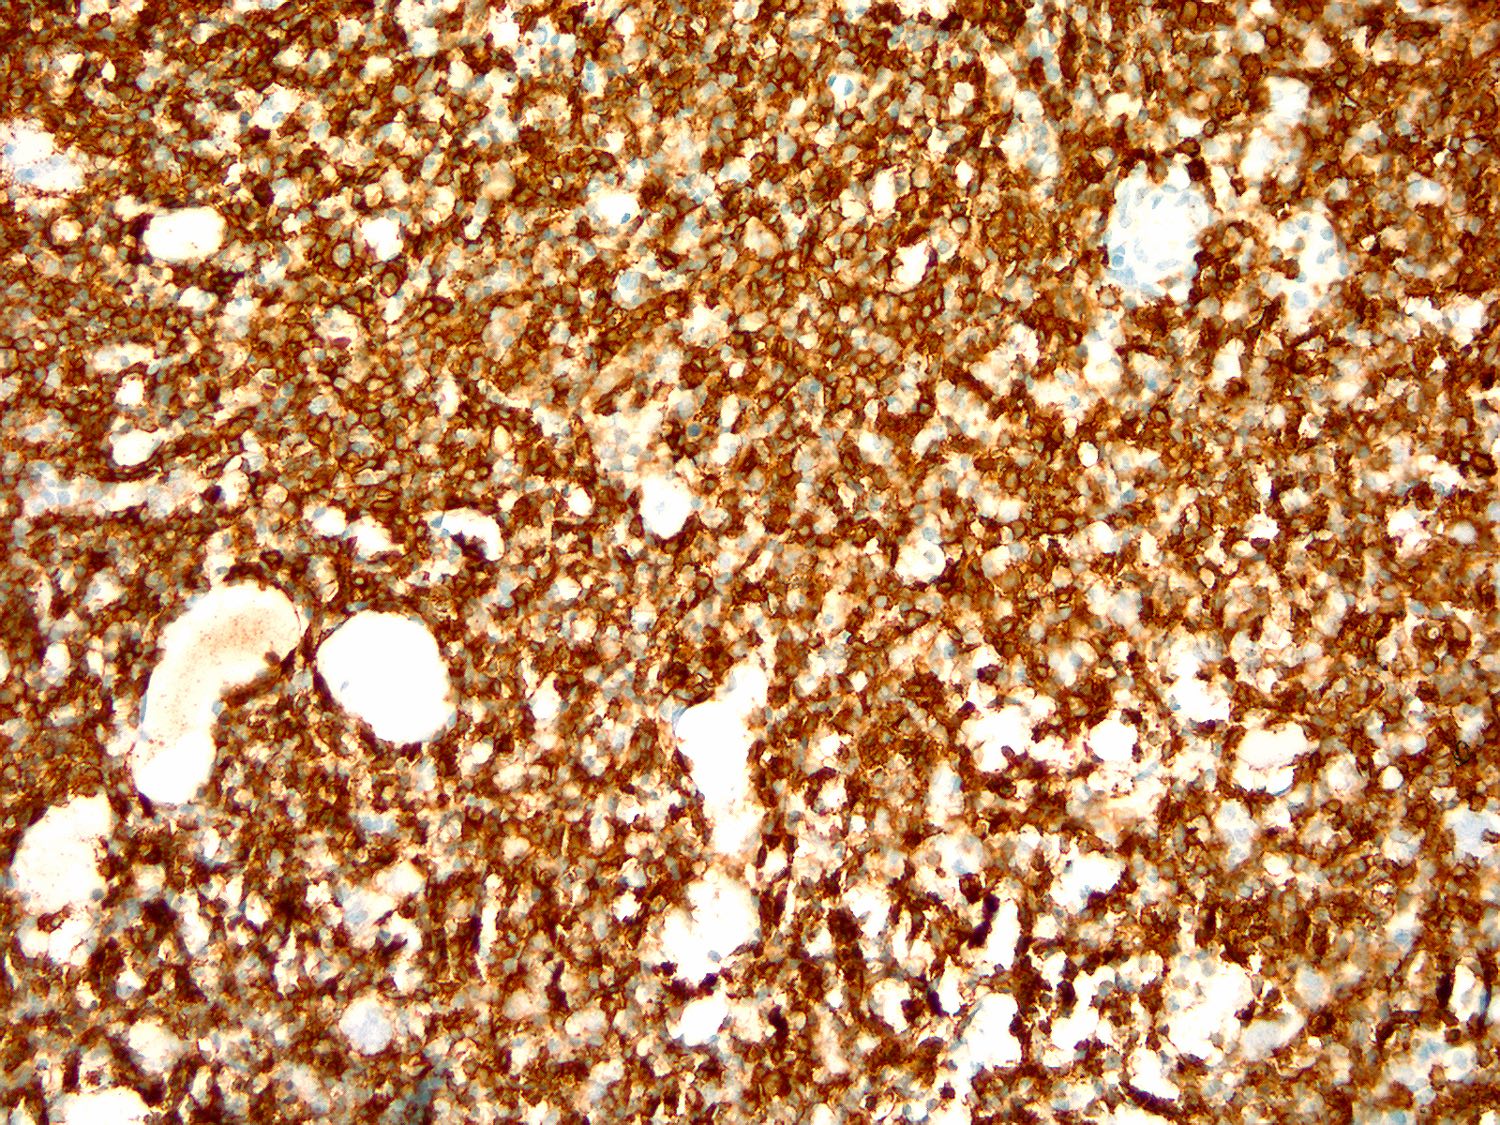

Microscopic (histologic) images

Contributed by Ling Zhang, M.D.

Positive stains